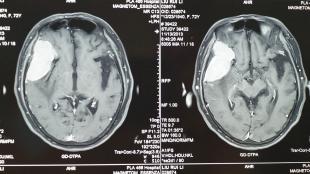

患者女,72岁,头痛,癫痫大发作,行颅脑CT及MRI检查,发现右侧额颞部巨大占位。检查,发现占位为起源于蝶骨嵴的脑膜瘤,直径约7**3cm,侵蚀颞骨、蝶骨,向内生长压迫脑组织致使中线结构移位,并与大脑中动脉、侧裂静脉等重要结构关系密切。现颞骨鳞部已被肿瘤组织侵透,肿瘤与正常脑组织粘连,正常结构已完全移位无法辨别。神经外科专家顾建文副院长及周岩博士,采用显微外科手术,经过1小时零8分钟的显微操作,将肿瘤基地部离断,最终将肿瘤完整切除,未损伤脑组织及大脑中动脉、侧裂静脉等重要结构,术后患者恢复满意,无明显不适。

5.CT和MRI扫描 可确定肿瘤的部位和大小,绝大多数可作出定性诊断。CT扫描示边界清晰的均匀高密度影,增强后显著。少数呈混合密度或低密度改变。MRI见肿瘤多数呈等信号,增强后明显强化。

1.CT扫描可见到以蝶骨嵴为中心的球形生长的肿瘤边界清楚,经对比增强后肿瘤影明显增强,如肿瘤压迫侧裂静脉,脑水肿较显著。

2.MRI扫描MRI对诊断本病是有意义的MRI可以显示肿瘤与蝶骨翼和眼眶的关系骨质破坏情况等。尤其是对内侧型的蝶骨嵴脑膜瘤MRI还可以提供肿瘤与颈内动脉的关系有时肿瘤将颈内动脉包裹在内或肿瘤附着在海绵窦上这些情况对手术切除肿瘤均有重要的参考价值增强后的MRI图像更清晰。

4.MRI 蝶骨嵴脑膜瘤在T1WI和T2WI上呈低信号或中信号,增强明显。和CT相比,MRI对于体积较小的肿瘤显示较好。颅内恶性脑膜瘤可侵及眶内、颅内,呈多发肿瘤。